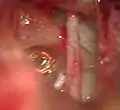

Mise en place de la prothèse accrochée sur la branche descendante de l'enclume droite (vue endoscopique)

Mise en place de la prothèse accrochée sur la branche descendante de l'enclume gauche (vue microscopique)